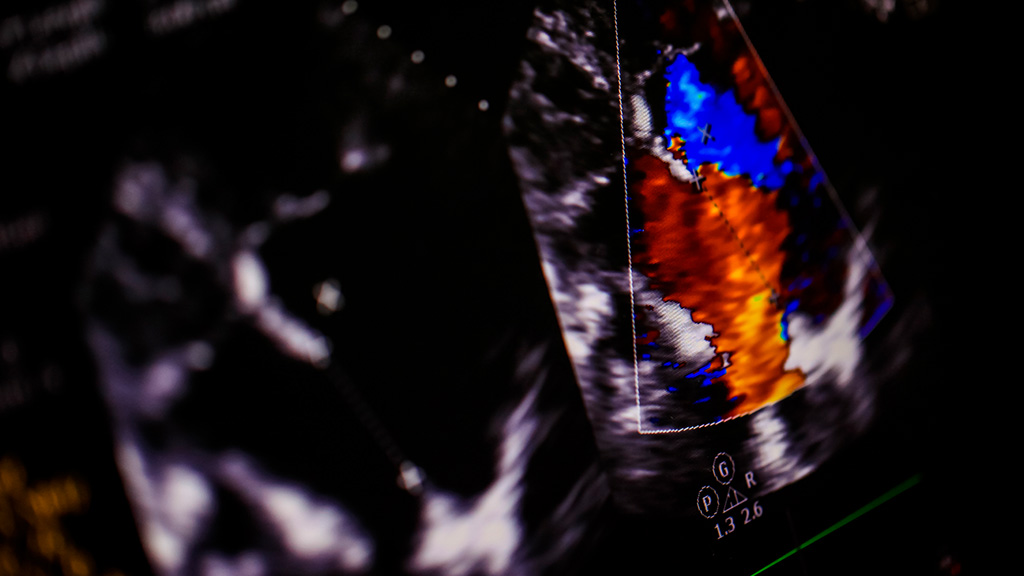

Ultrasonido Obstetrico Gemelar Doppler Color